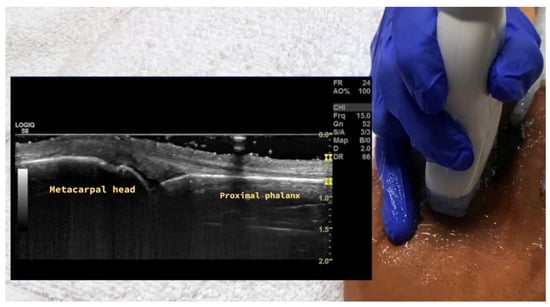

4.1. Evaluation of the Fingers

4.1.1. Dorsal Aspect

4.1.2. Volar Aspect